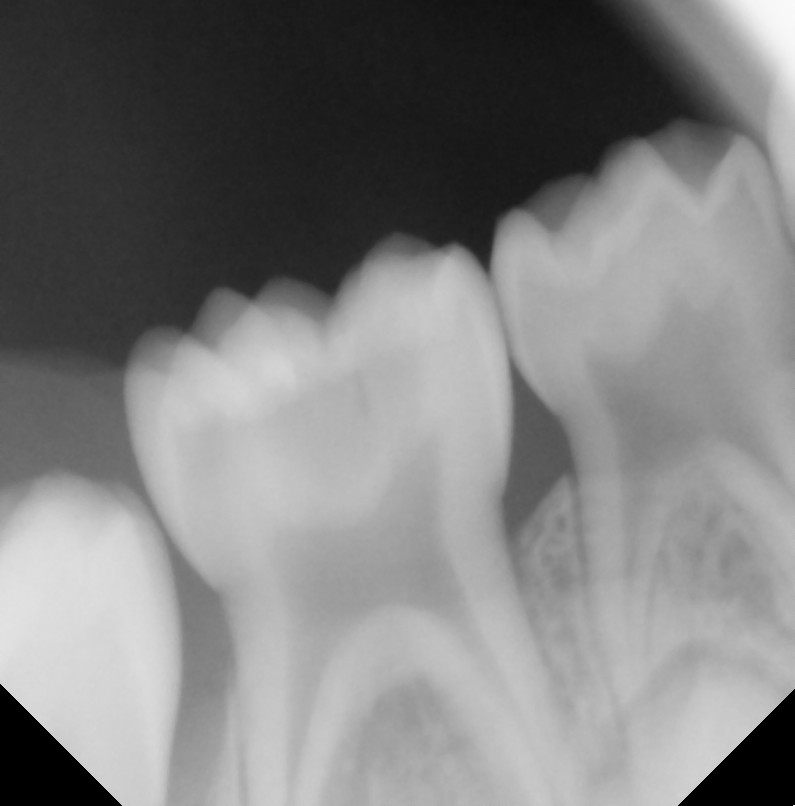

After After

Before Before